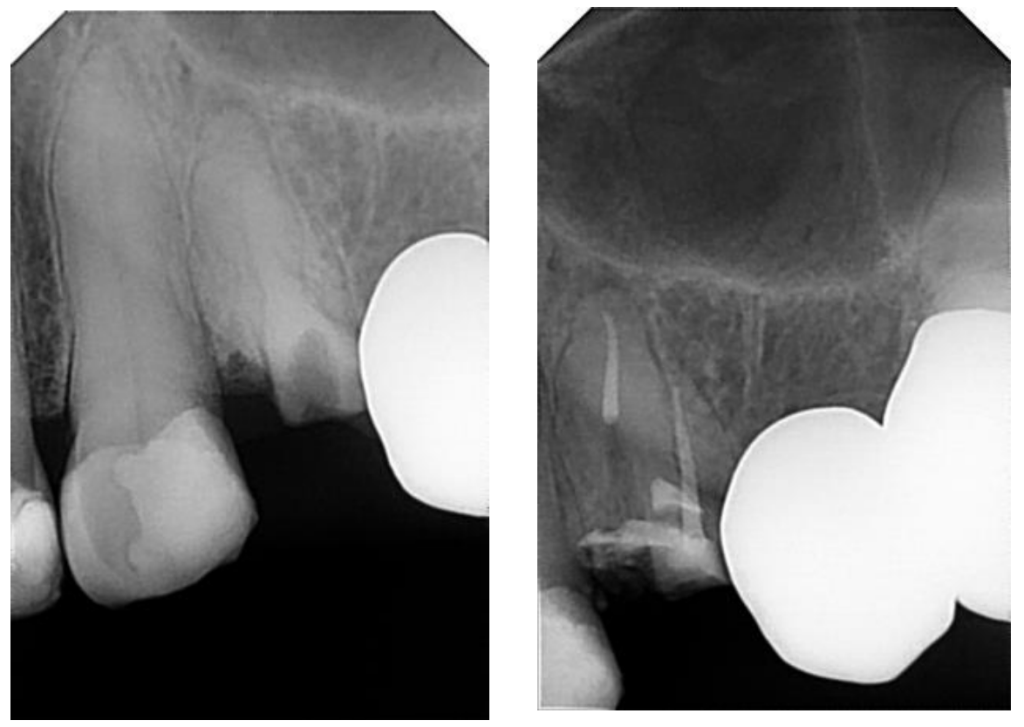

Case Study: Endodontics - Root Canal Treatment

Before: The patient was diagnosed with asymptomatic apical periodontitis in multiple teeth. The condition showed radiographic signs of infection at the root apex, though without significant pain at the time of diagnosis.

Treatment: A complete root canal therapy was performed using advanced instrumentation (WaveOne Gold system), active irrigation protocols, and biocompatible sealing materials. This ensured thorough cleaning, disinfection, and sealing of the canals to prevent reinfection.

After: The final radiograph shows well-sealed canals and elimination of the infected tissue. This treatment preserved the natural teeth, relieved the risk of future pain, and restored full dental function — avoiding the need for extraction and maintaining the patient’s oral health.